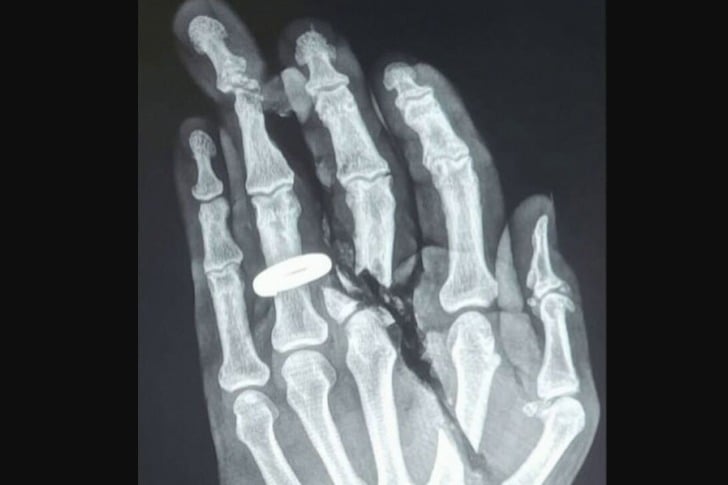

#24 Tischkreissäge?

Mich würde wirklich interessieren, was so einen sauberen Schnitt verursachen könnte, damit ich das natürlich vermeiden kann.